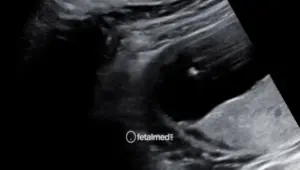

Dopplerfluxometria Obstétrica

Dopplerfluxometria obstétrica para avaliação do fluxo sanguíneo fetal e placentário. Monitoramento da vitalidade fetal em Curitiba.

A dopplerfluxometria obstétrica é um exame que avalia o fluxo sanguíneo nos vasos fetais, placentários e maternos. Utilizando tecnologia Doppler, mede a velocidade e resistência do sangue em artérias e veias específicas, fornecendo informações fundamentais sobre o bem-estar fetal.

É um dos exames mais importantes para o acompanhamento de gestações de alto risco, especialmente em casos de restrição de crescimento fetal e pré-eclâmpsia.